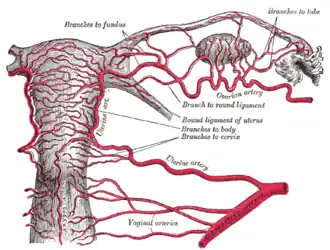

| Vascularização | artéria ovariana, artéria uterina, helicine branches of uterine artery |

As artérias dos órgãos internos femininos, vistas por trás

As artérias dos órgãos internos femininos, vistas por trás -